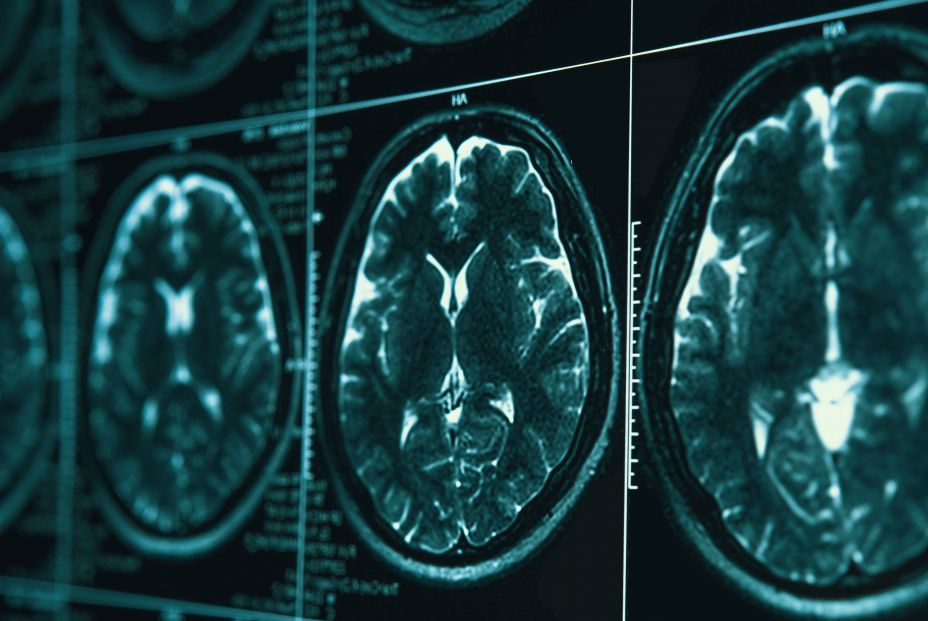

Una vez localizado el punto exacto del cerebro sobre el que aplicar los ultrasonidos, gracias a la imagen radiológica de la anatomía del paciente previamente planificada por los radiólogos en una resonancia magnética de tres teslas, se incrementa la temperatura hasta los 60º centígrados para la ablación o eliminación de las neuronas responsables del temblor.

En este procedimiento resulta muy importante la planificación que lleva a cabo el radiólogo “porque las imágenes de alta resolución y corte fino de las estructuras del cerebro que proporciona la resonancia de tres teslas guían los haces de ultrasonidos hacia el punto exacto donde se encuentran las neuronas responsables del temblor para su ablación asegurando, a su vez, el resto de estructuras cerebrales”, ha detallado el radiólogo Carlos Pérez.